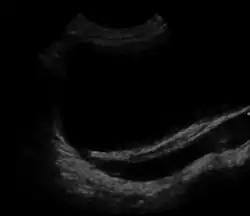

A DRM é geralmente diagnosticada por exame de ultrassom antes do nascimento. A idade média no momento do diagnóstico pré-natal é de cerca de 28 semanas.[3] Deve-se fazer uma análise microscópica da urina em indivíduos com provável rim displásico multicístico.[4] Uma meta-análise demonstrou que a DRM unilateral ocorre com mais frequência em homens e a maior porcentagem ocorre no lado esquerdo do corpo.[11]